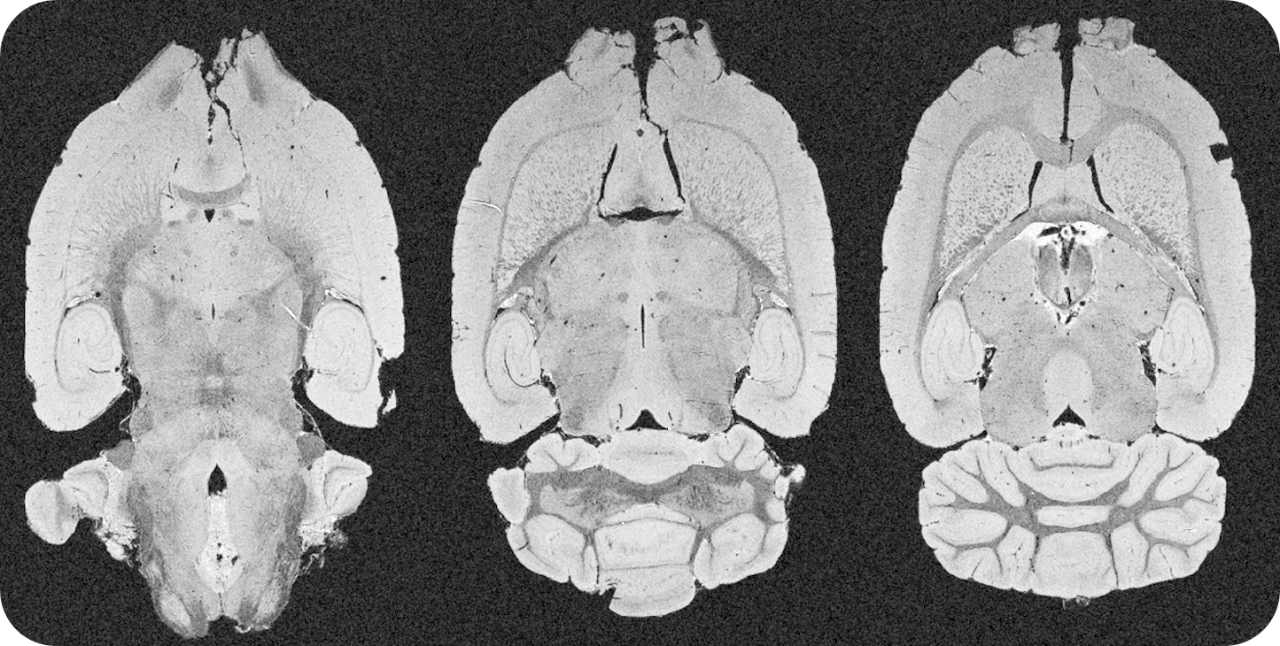

The ultra-high field of the BioSpec 152/11 provides extreme sensitivity for greatest resolution. Its streamlined design for mice studies makes handling simple, while its powerful software guarantees best results. It can be equipped with the MRI CryoProbe to increase sensitivity even further and together with the gradient strength of up to 1000 mT/m, highest resolution is achieved. It is built with nitrogen-free Ultra Shielded and helium Refrigerated (US/R) magnet technology for long service intervals

• Crisp and highly resolved images with native gradient strength of 740 mT/m, upgradable to 1000 mT/m

• MRI CryoProbe for exceptional increase in sensitivity